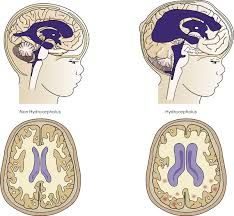

ولفت الى أن الاستسقاء الدماغي هو تراكم السائل الدماغي الشوكي في التجاويف (البطينات) الموجودة في عمق الدماغ مما يؤدي إلى زيادة في حجم هذه البطينات،وبالتالي تحدث ضغطاً على أنسجة الدماغ.

وقال: يتم انتاج السائل الدماغي الشوكي بواسطة خلايا متخصصة موجودة داخل البطينات الدماغية ويتم افرازه إلى تجاويف هذه البطينات،وفي الوضع الطبيعي يتدفق هذا السائل من خلال البطينات ويدور حول الدماغ والحبل الشوكي،ولكن الضغط الذي يحدثه فرط السائل الدماغي الشوكي يمكنه أن يلحق ضرراً بأنسجة الدماغ مسبباً مجموعة من الأعراض مرتبطة بوظائف الدماغ.

أضاف: يتم تشخيص الاستسقاء الدماغي عن طريق التاريخ المرضي والفحص السريري للمريض،ثم عمل تصوير شعاعي لأنسجة الدماغ بالأشعة المقطعية أو الرنين المغناطيسي، لافتاً الى ان علاج الاستسقاء الماغي هو علاج جراحي إما بزراعة تحويلة لتحويل السائل الماغي الشوكي إلى البطن،أو عن طريق المنظار الجراحي وعمل فتحة صغيرة في قاع البطين الدماغي الثالث.